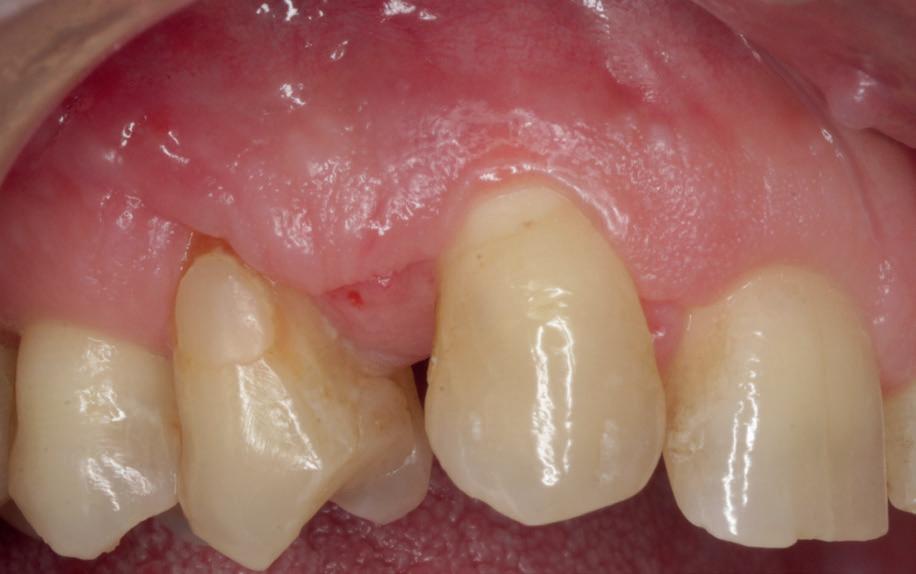

Stap 3: Kies de matrix

Kies de juiste hoogte matrixband van het V3 systeem. Ideaal gezien steunt de matrixband op het tandvlees en eindigt de bovenzijde van de matrix ter hoogte van de randlijst van het element (afbeelding 5).

Stap 4: Plaats de gemodificeerde wig

Plaats een afgeknipte wig. In bijna alle gevallen gebruik ik de Wizard Wedge Wide base. Hierbij is het belangrijk dat de wig geplaatst wordt aan de zijde waar het minste tandweefsel verloren is gegaan. Zorg ervoor dat de wig direct vastloopt. Indien dit niet het geval is, dan dient de wig ingekort te worden met behulp van een schaartje en opnieuw geplaatst te worden. De wig sluit dus de bodem van de box niet af, zoals je normaal gesproken met een wig wel doet (afbeelding 6 en 7).